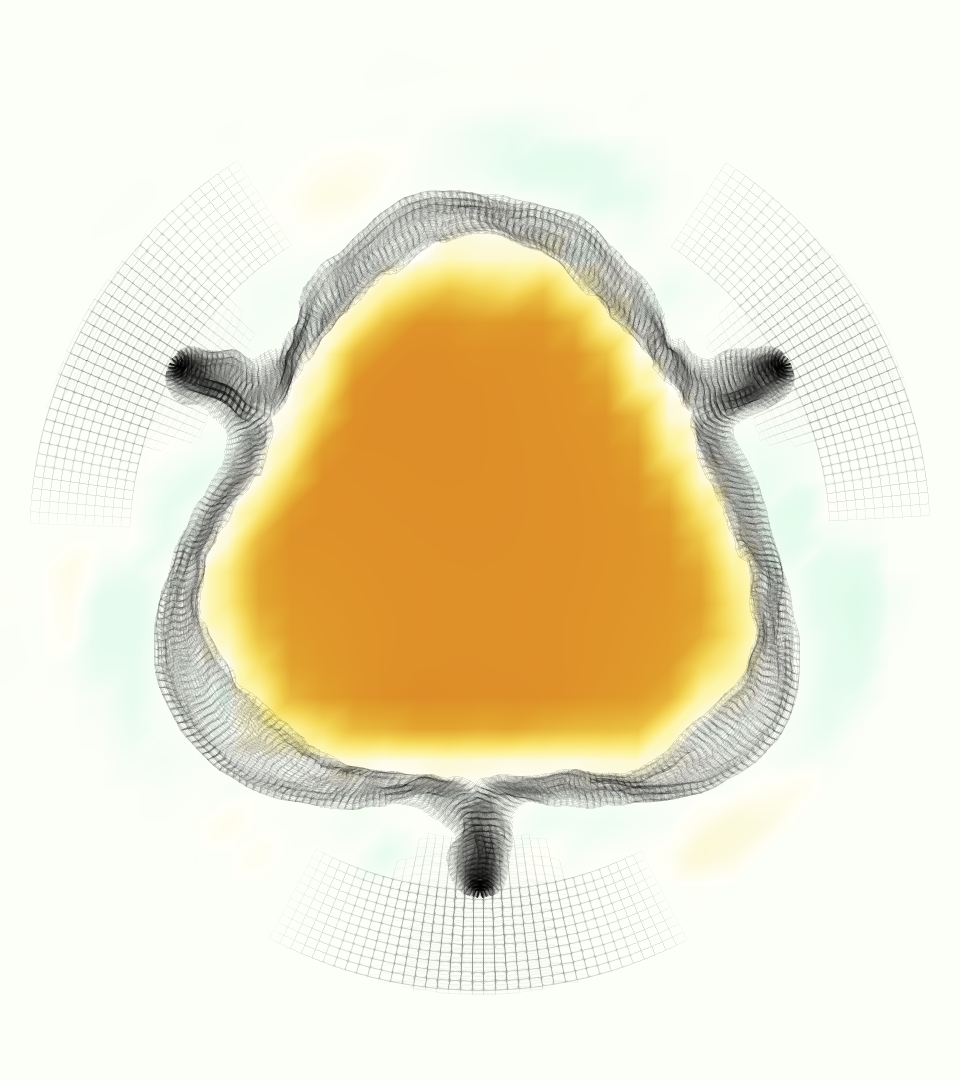

The gross morphology of the model valve that emerged from this process is shown in Figure 4. The free edge was 2.87 cm, corresponding to 3.3 cm in the predicted loaded configuration. After the pinching the leaflets together at the commissures, this left approximately 2.1 cm of free edge rest length per leaflet free to move independently of the other leaflets, within measurement error of ±0.1 cm from the free edge length of 2.2 cm measured on the prostheses. The leaflet rest height was 0.94 cm corresponding to a predicted loaded height of 1.44 cm. The measured leaflet height of 1.3 cm is nearly the predicted loaded height of 1.44 cm, which may be because the leaflets are so compliant in the radial direction, that pulling them flat to measure them achieved substantial stretches. The fiber orientation of the model runs from commissure to commissure and qualitatively matches experimental observations [38], though direct quantitative comparison is beyond the scope of this work. One minor limitation is that we do not add bending rigidity to the leaflets, beyond what emerges from the thickening process described above, and thus may not accurately capture leaflet flutter or other similar behaviors. Based on the thickness of mm, we estimated the mean tangent modulus at the predicted loaded stretches as dynes/cm2 circumferentially and dynes/cm2 radially. The prosthetic valve tissue is fixed in glutaraldehyde, and literature values for the fully-recruited circumferential tangent modulus of fixed porcine aortic valve tissue vary widely. Based on the experimental measurements of Billiar and Sacks and their constitutive law for valves fixed under 4 mmHg of pressure, we evaluated their constitutive law at the relevant stretches and and estimated the circumferential tangent modulus to be dynes/cm2 [6]. Rousseau et al. reported moduli ranging from to dynes/cm2, depending on the applied preload during fixation [36]. Sung et al. reported moduli ranging from to dynes/cm2, depending on fixation pressure [43]. Thus our estimated tangent modulus falls within the range of existing studies, so we considered our resultant modulus in good agreement given the complexity of the steps involved, phenomenological nature of the constitutive law and uncertainties in experiments. We do not have access to the precise material properties of the prosthetic valve, and further, the only literature we could find on the material properties of a similar prostheses reported the tangent modulus at one particular loading, which did not appear to be at a relevant stretch for comparisons with our model [19]. Thus, our model has material properties in a reasonable range for a fixed aortic valve prostheses (placed in the pulmonary position in our simulations), but it does not directly model the material properties of the prostheses.

The emergent hemodynamics showed excellent qualitative agreement with experiments. Slice views of the axial component of fluid velocity ( component) in the sagittal plane that cuts through the center of the vessel, parallel to the flow direction, are shown in Figure 5. The flow in both the simulation and the experiment began to accelerate at the same time, with a jet forming through the open valve leaflets. The velocity, angle, and shape of the jet agreed well between the two cases during systole. The simulation captured the slight upward angle of the jet, which was not fully centered in the vessel. It also matched the location where the jet impacts the wall and the slower speed of the jet as it turns with the MPA downstream. As the flow decelerated, the fluid along the interior curve of the vessel reversed first while forward flow persisted where the jet was strongest, as seen in both the simulation and experimental results.

In both the experiment and the simulation, a separation region of reverse flow developed along the interior curve of the vessel under the core jet through the valve. The reverse flow began to develop at the same time in the cardiac cycle and grows throughout systole. The simulation lacked reversed flow in the entire region where reversed flow was present in the experiment, but this region developed some flow separation and had much slower flow than elsewhere in the vessel. Thus, the simulation captured that this is a distinct region from the core jet through the valve opening. There was a smaller amount of slower and slightly reversed flow along the outer curve of the vessel, close to the valve annulus and scaffold support. This region was well-matched between the experiment and the simulation.

Slice views of the (axial) component of fluid velocity in the axial plane, orthogonal to the flow direction, show that the simulation replicated the development of the jet over the cardiac cycle. At each phase, the simulation matched the forward speed of the core of the jet and the locations of reverse flow back towards the valve annulus. While there are some differences in the shape of the jet at certain phases and locations, the simulation clearly produced the general dynamics of the cardiac cycle that are seen in the experiment.

At = 0, the axial slice directly at the valve annulus shown in columns 1 and 2 in Figure 6, there was excellent agreement between the simulation and experiment over the cardiac cycle in the speed and shape of the jet through the valve. In both cases, the axial velocity increased as the flow accelerated during systole and the valve leaflets opened, then decreased during diastole with slight negative velocity before the valve leaflets were fully closed. The forward flow through the valve annulus did not form a full circle, but rather developed a triangular shape with a point of the triangle forming along the interior curve of the vessel, at the bottom of the axial slices. At = 0, the points of this triangular jet shape aligned with the commissures of the valve. This shape persisted during peak systole and was well-matched by the simulation.

The axial slice = 0.625 cm, shown in columns 3 and 4 in Figure 6, cut through the support scaffolding of the valve and the leaflets when they are open. In the experimental data, the shape of the jet changed as it moved downstream. A triangular shape occurred, but the points were then aligned with the middle of each open leaflet as opposed to the commissures. Those points were also more rounded than they were at = 0. The peak velocity of the jet was faster at = 0.625 cm than at = 0, as the flow accelerated through the open valve leaflets. The simulation produced these features at = 0.625 cm. The triangular shape of the jet shifted similarly, and its speed increased compared to the upstream slice. As the flow decelerated into diastole, the jet shape remained roughly triangular but diminished in intensity before disappearing after valve closure.

The jet continued to develop at = 1.25 cm, an axial slice immediately downstream of the valve scaffolding and open leaflets, shown in columns 5 and 6 in Figure 6. In the experimental data, the points of the triangular jet shape extended further towards the vessel wall. In addition, regions of reversed flow developed in the locations downstream of the commissures, resulting in curved sides to the shape of the jet. Each tip of the jet was unique, due to variations in the individual leaflets in the physical bioprosthetic valve. These variations are apparent in the velocity fields, possibly because the jet edges are similar enough cycle to cycle that irregularities are still being captured even with phase averaging. Further discussion of these features can be found in Schiavone et al. [39], which showed that the jet tip shapes occurred in different pulmonary anatomies, demonstrating that they were likely due to inherent properties of each leaflet. The leaflets in the mathematical model of the valve are identical, so these nuances in leaflet variation could not be replicated. The simulation did capture some of the extension of the tips of the jet, as they were closer to vessel wall at slice = 1.25 cm than = 0.625 cm. The curves in the triangular sides of the jet were also present in the simulation, though they were less pronounced than the experimental data. At both = 0.625 cm and = 1.25 cm, the jet shape in the simulation was smoother than the jet in experiment. It is possible that the free edges of the leaflets in the mathematical model are not fully replicating the behavior of the physical leaflets of the bioprosthetic valve, in particular the amplitude or frequency of leaflet flutter, leading to the variations seen in the jet shape at = 1.25 cm downstream of the leaflet edges. The simulation, however, does capture the key features of the triangular shape and speed of the jet. Overall, qualitative comparisons demonstrated that the simulation reproduced key features of the flow during systole and diastole.

The simulated velocity fields showed excellent qualitative agreement with the experimental velocity. Many features of the flow that were present in the experimental measurements also appeared in the simulations, including a large jet which angled up downstream of the valve and the appearance of a triangle-like shape in the jet. A recirculation zone appeared downstream, though the precise region of recirculation showed only some agreement at some points in time. We prescribed the experimentally measured pressures (subject to minor processing as described in Section 3.3), and the emergent flow rates matched those of the experiments.